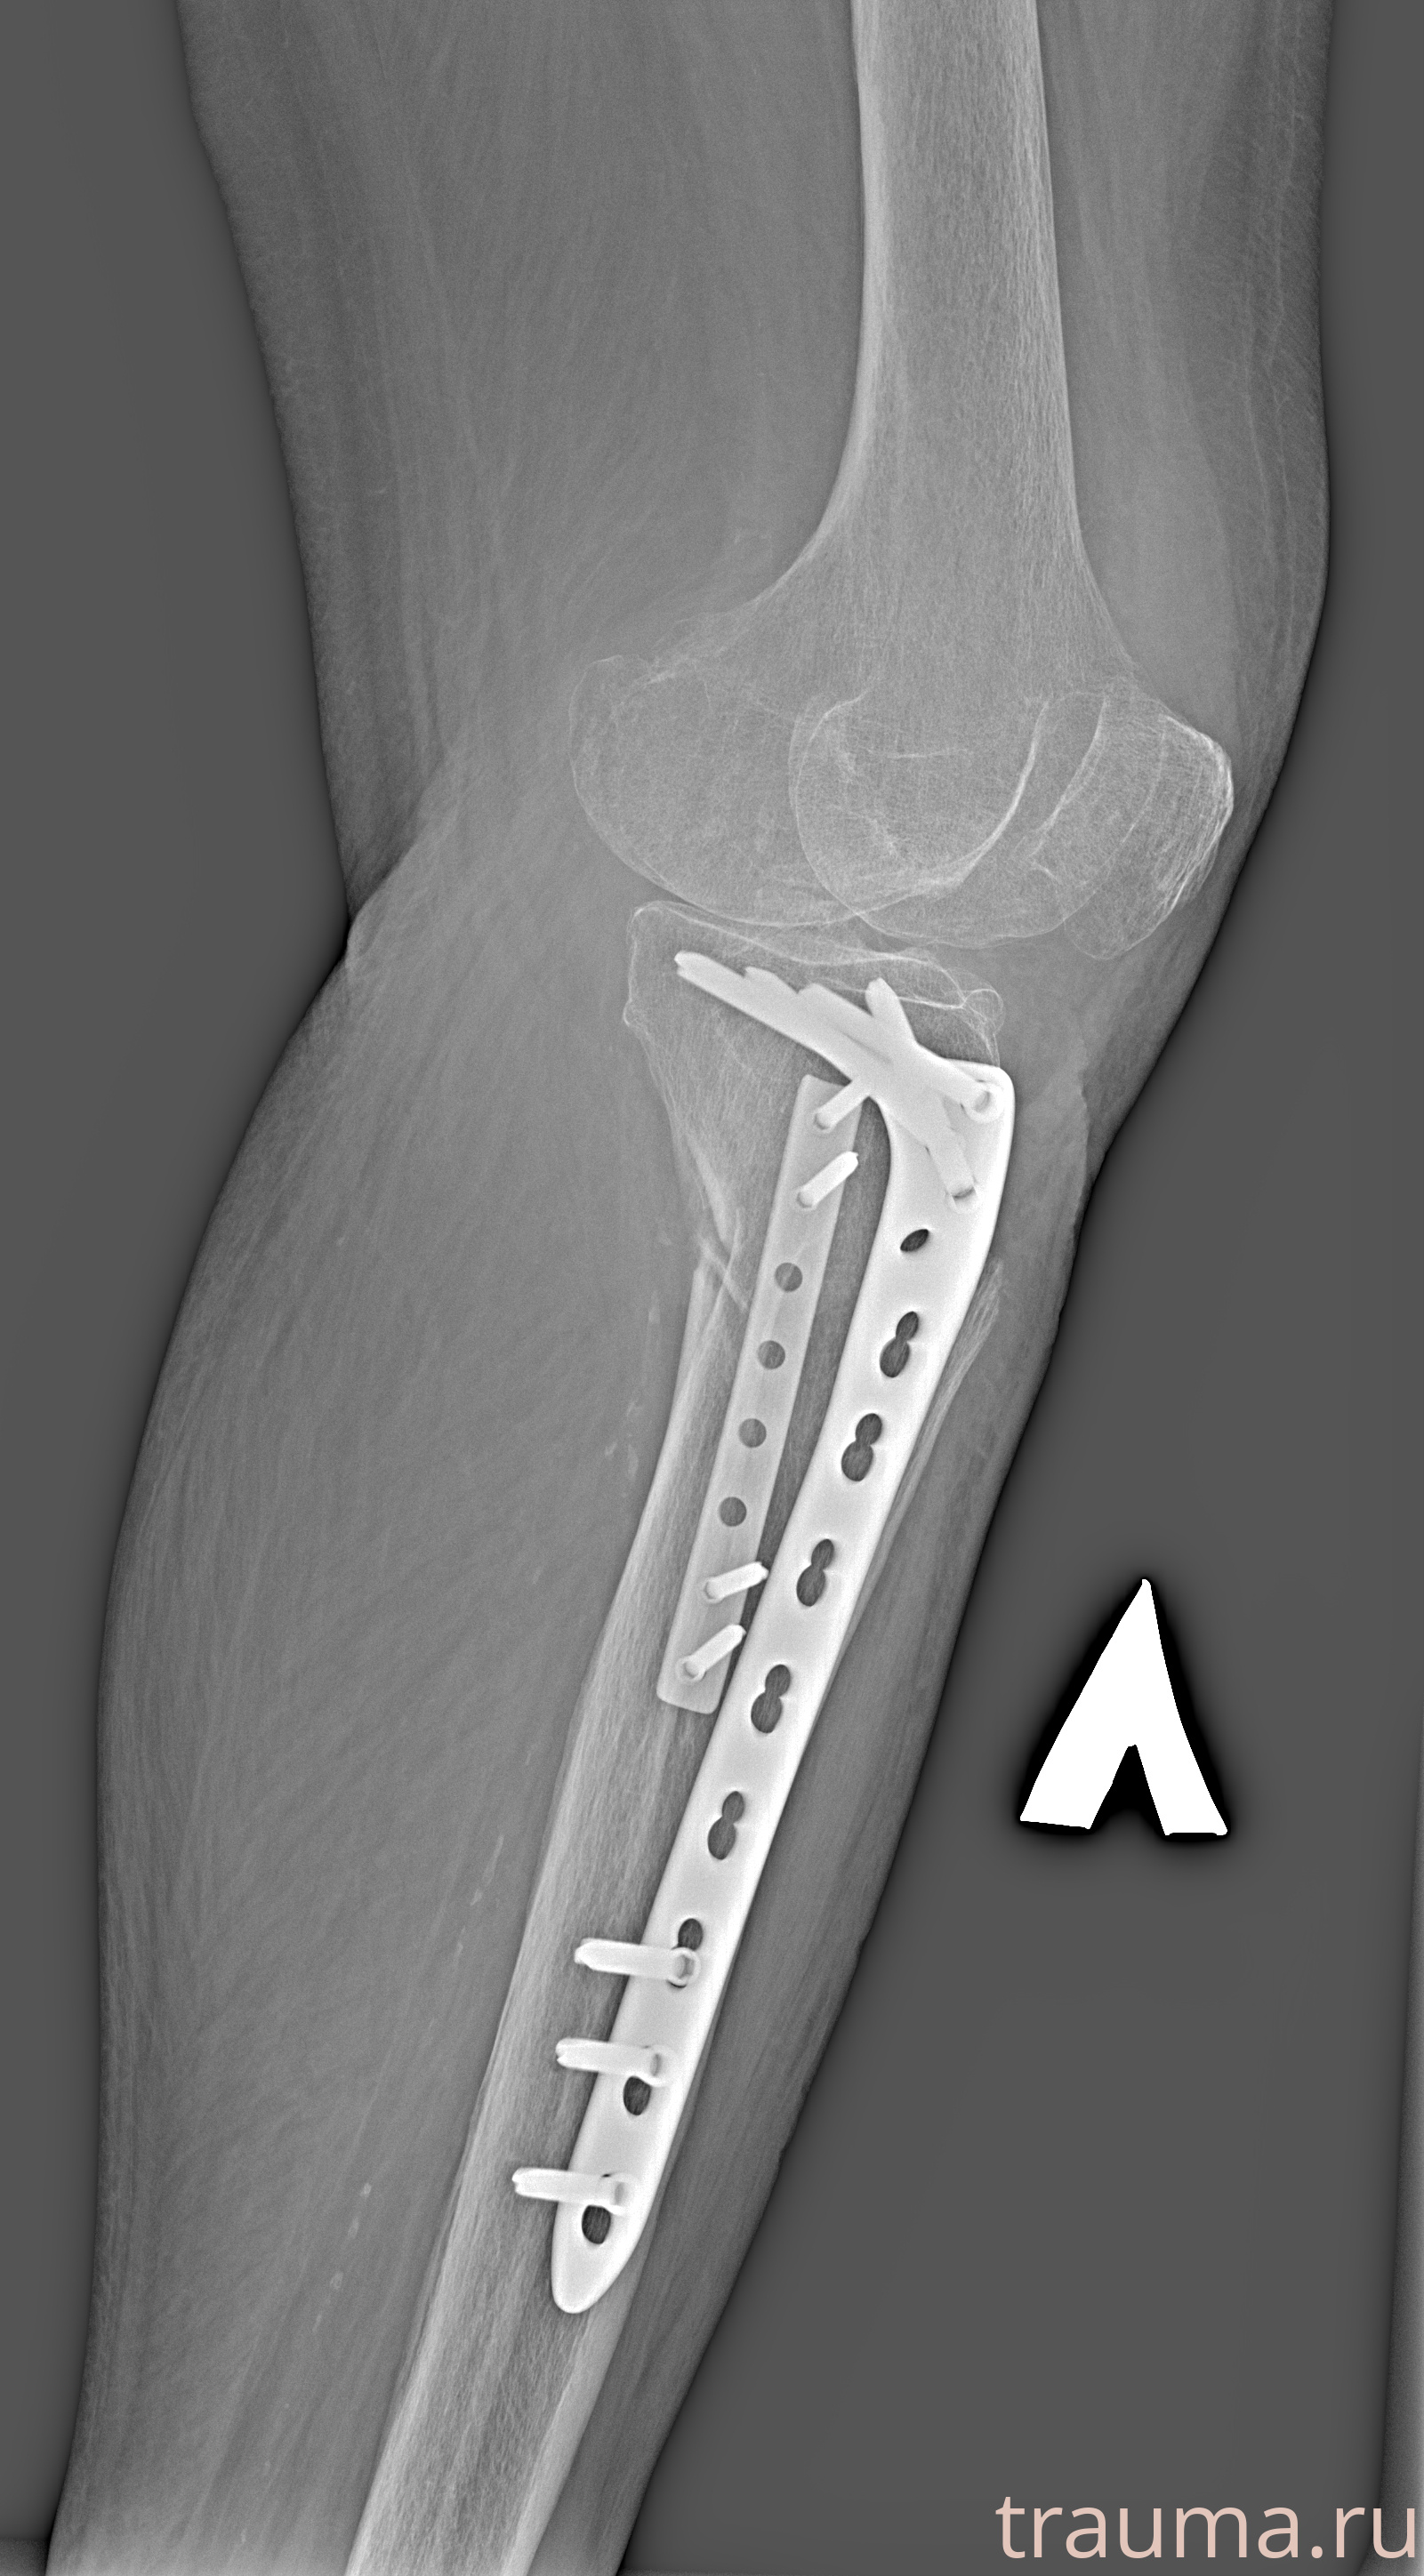

Рентгенограммы

Рентген на дому: по вашему адресу приезжает врач-рентгенолог, травматолог-ортопед с мобильным рентгеновским аппаратом, проводит диагностику травмы или заболевания, делает необходимые рентгенограммы, дает рекомендации по дальнейшему лечению. Получить качественные снимки в домашних условиях возможно благодаря уникальной методике, разработанной МосРентген Центром для института  Склифосовского